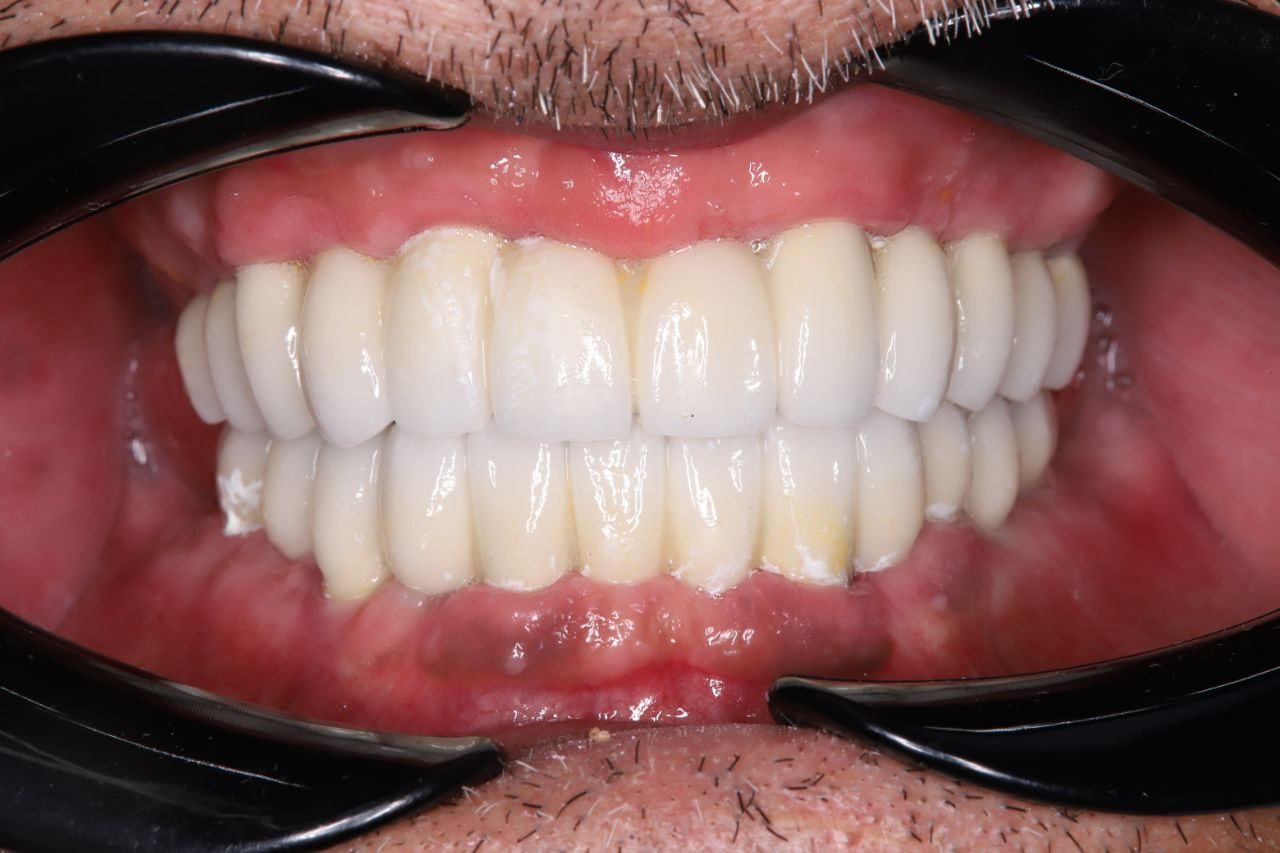

Результат проделанной работы

Установлено 6 дентальных имплантов. После хирургического этапа были изготовлены и зафиксированы временные коронки (временная ортопедическая конструкция) на период приживления имплантов. После завершения остеоинтеграции изготовлены и установлены постоянные коронки из диоксида циркония.

Результат — восстановлены функция жевания и эстетика улыбки.